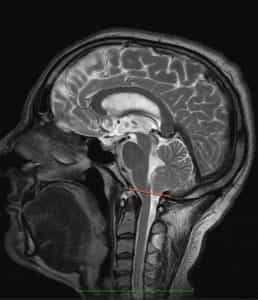

Определение

Синдром Арнольда Киари I типа состоит в опущении нижней части мозжечка - миндалин мозжечка - в затылочное отверстие и позвоночный канал при отсутствии других мальформаций, связанных со спинным мозгом. Иногда считают, что опущение миндалин мозжечка должно быть более 5мм, иногда - больше 3мм, для других опущение начинается с 0мм, когда миндалины находятся на уровне границы затылочного отверстия, при наличии соответствующей клинической картины.

Рисунок 1.- На схеме показано опущение миндалин мозжечка и увеличение надмозжечкового пространства из-за смещения всего мозжечка к затылочному отверстию. Синдром Арнольда Киари I.